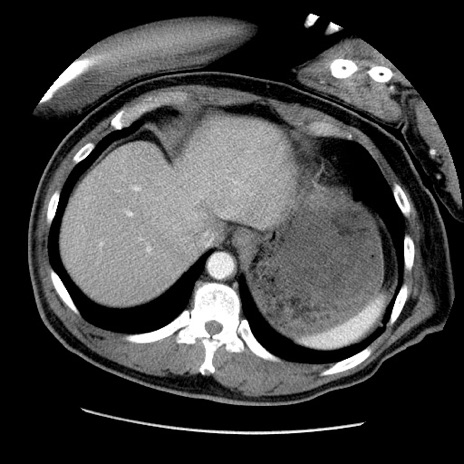

症例22(横断像)

【症例】50歳代男性

【主訴】腹痛

【現病歴】AVMからの被殻出血のため回復期リハ病棟入院中。 本日午後3時頃急に下腹部痛が出現した。

【既往歴】AVM、被殻出血、虫垂炎、高血圧

【身体所見】意識晴明、左半身不全麻痺、会話の理解は良好、36.5°C、腹部:膨隆、全体に板状硬、下腹部正中に圧痛点あり、反跳痛-、筋性防御不明、右下腹部にope scar

【データ】WBC 9400、CRP 0.06